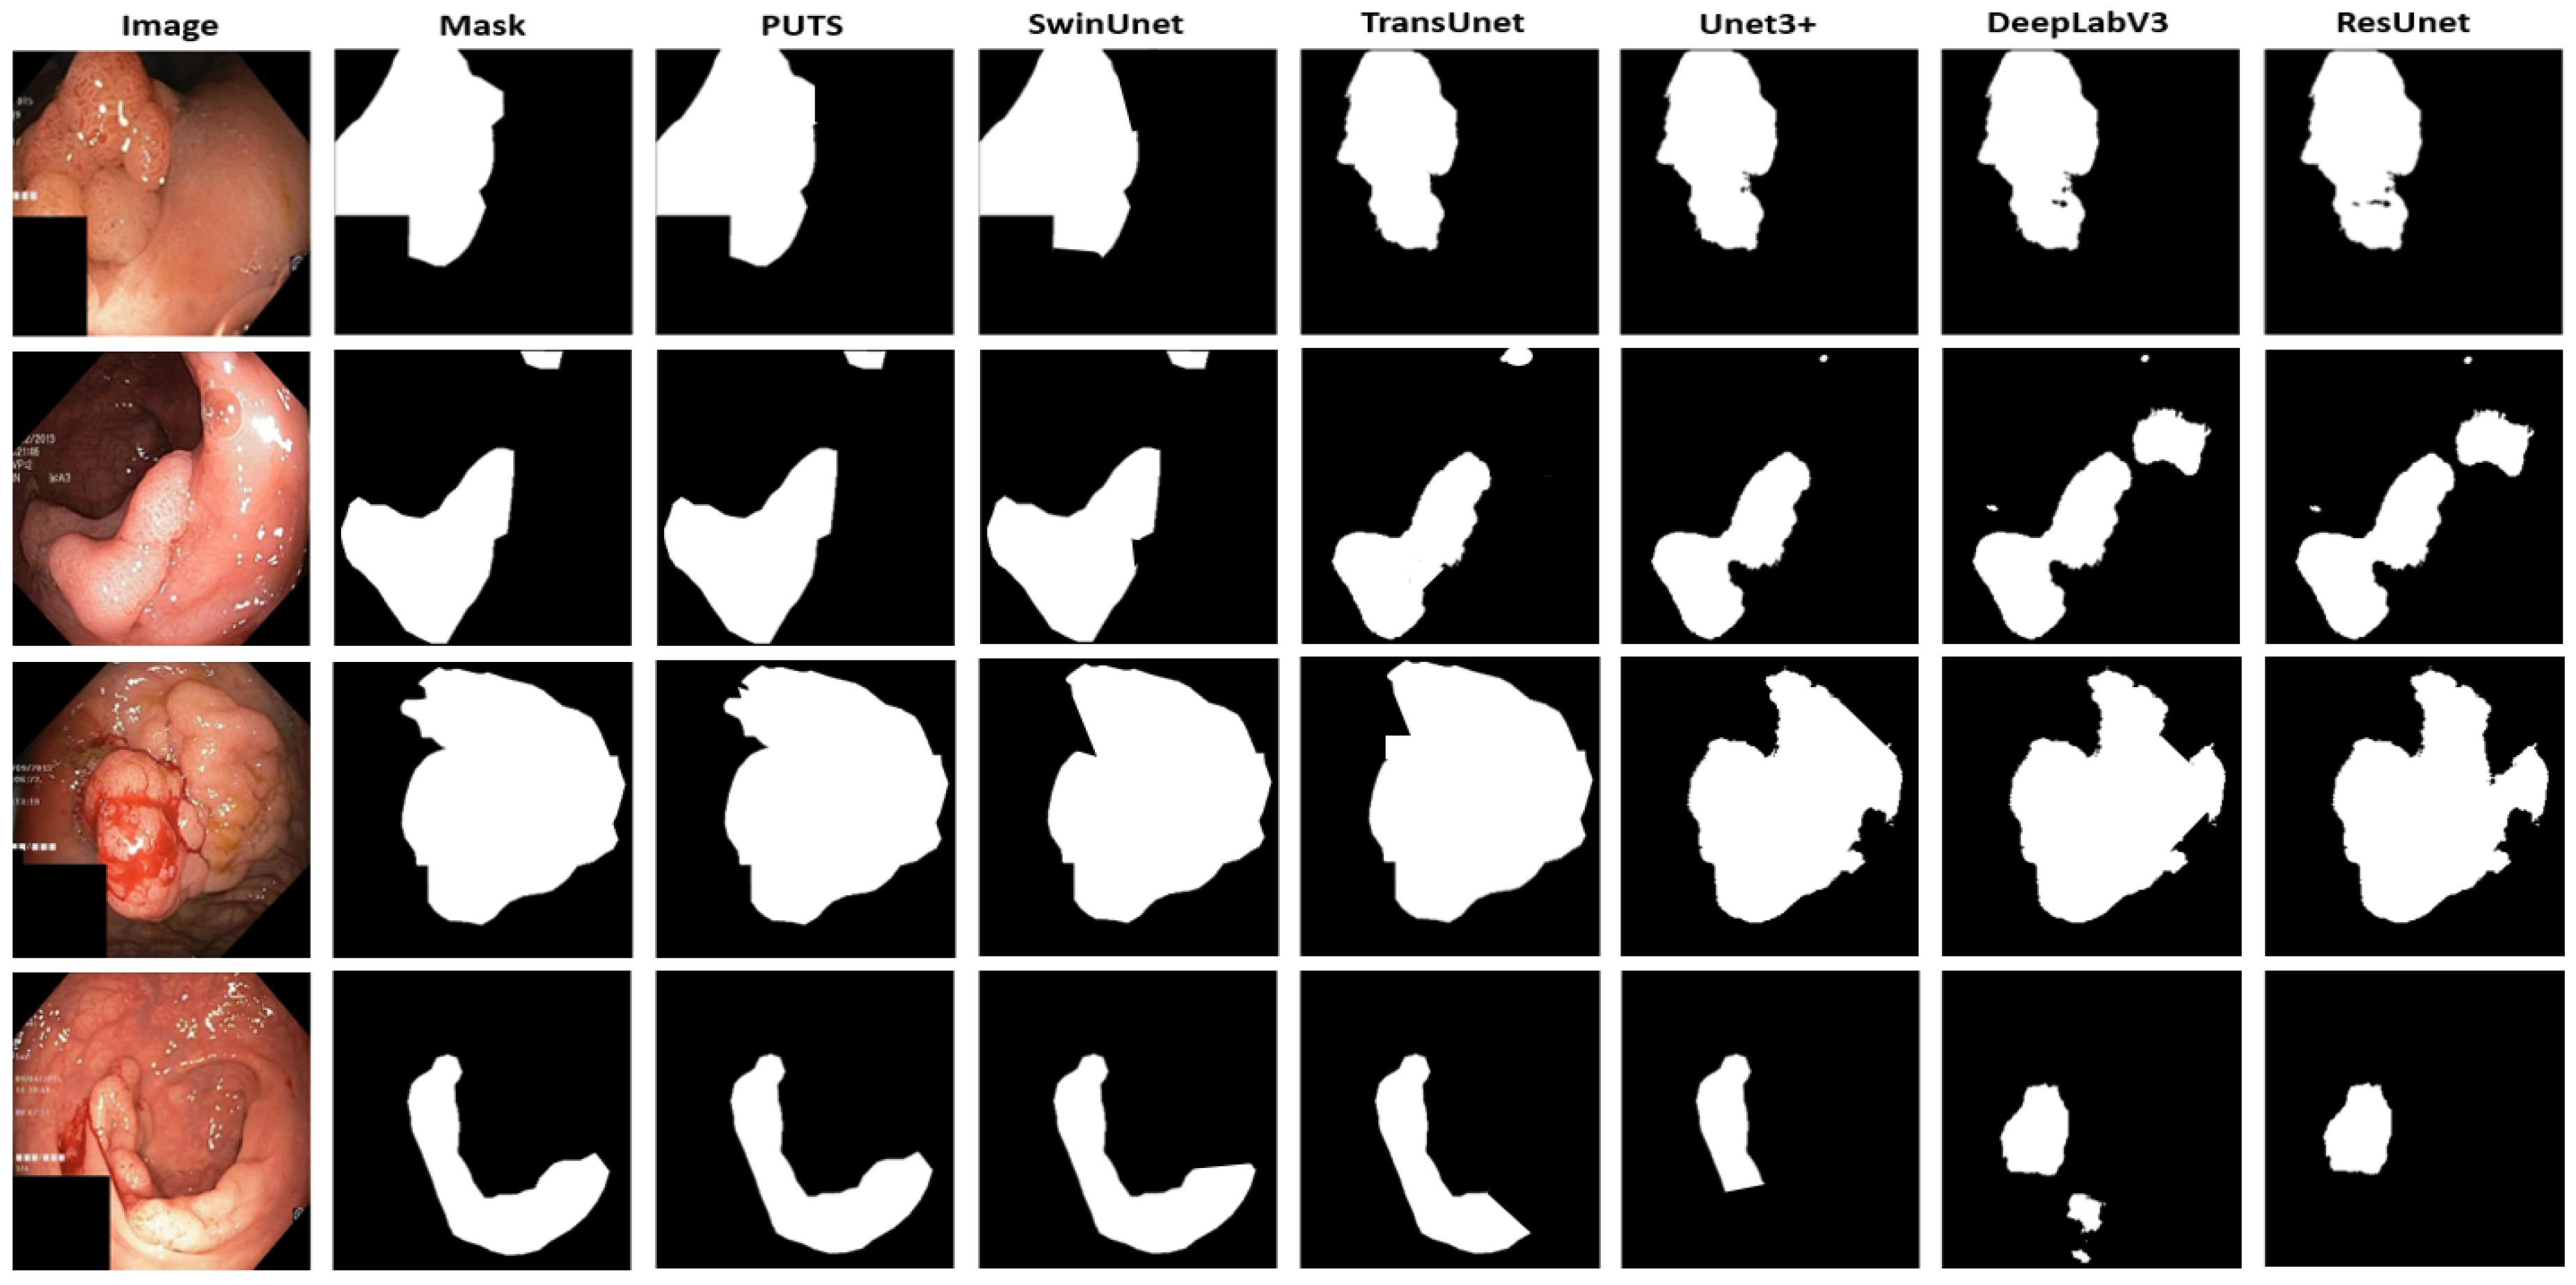

- PUTS: A novel Swin-Unet transformer-based polyp segmentation model;

3.2. PUTS: Vision Transformer-Based Polyp Segmentation

3.2.2. PUTS Architecture

4.2. Polyp Segmentation Performance Results